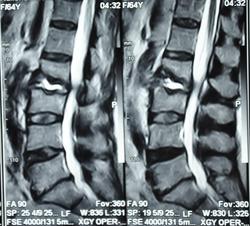

Можно гадать, но без клиники и анамнеща никак. Исходя из картинок больше на пиогенный вроде. Хотя, и тубер может выглядеть так же.

Наверное, правильнее это можно назвать спондилодисцитом ( не туберкулезной этиологии)

Как-то  ( боюсь повториться, но что делать!) наш преподаватель по рентгенологии в Хабаровске говаривал:"Если больного принесли на носилках из-за невозможности движений, то это  пиогенныый ( гематогенный) спондилит, если пришел сам, на своих ногах, то туберкулезный."Еще нас учили, что размеры деструкции в одном позвонке при гематогенном поражении больше, чем в следующем позвонке, при туберкулезном-2 и более позвонка поражены одинаково;реактивный склероз  чаще встечается при гнойных процессах, при туберкулезе-как правило, не бывает; процесс при туберкулезе протекает медленнее,при гематогенном-может молниеносно ;наличие туберкулеза  других органов и систем ( не обязательно).

Мне видится здесь последствия зверского дисцита.  Предположу, ситуация не острая - данных за отек соответсвующих позвонков нет, хотя для убедительности нужен FatSat.  Из этого делаем вывод- на первое место исход воспаления, с формированием кистозных изменений, на второе - быть может нечто постравматическое с последующим, опять же, дисцитом.

При пункция патологического участка позвоночника - Лимфома позвоночника. Передан онкологам на лечение.

Уважаемый Николас, диагностировать лимфому по представленным сканам-высший пилотаж.Аксиалы, короналы напрочь отсутствуют-как можно обнаружить паравертебральный мягкотканный компонент ( если он имеет место быть, конечно)????.А вот явные признаки спондилодисцита имеются.

По мне так спондилодисцит. Характерный жидкостной сигнал в диске, деструкция смежных позвонков. А уж какой этиологии, это пусть клиницисты решают.